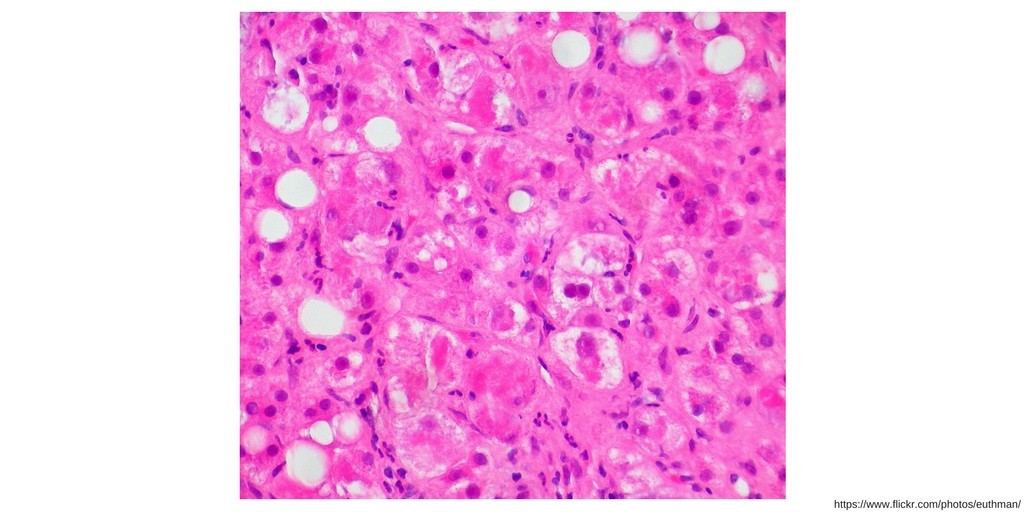

Episode 142: Amiodarone induced hepatotoxicity

In this episode, I’ll discuss amiodarone induced hepatotoxicity. Subscribe on iTunes, Android, or Stitcher Amiodarone is known to cause two distinct types of hepatoxicity: 1. Hepatotoxicity associated with long-term oral therapy 2. Hepatotoxicity associated with intravenous amiodarone Hepatotoxicity associated with long-term oral therapy Almost one-quarter of patients on long-term oral amiodarone therapy experience an asymptomatic […]